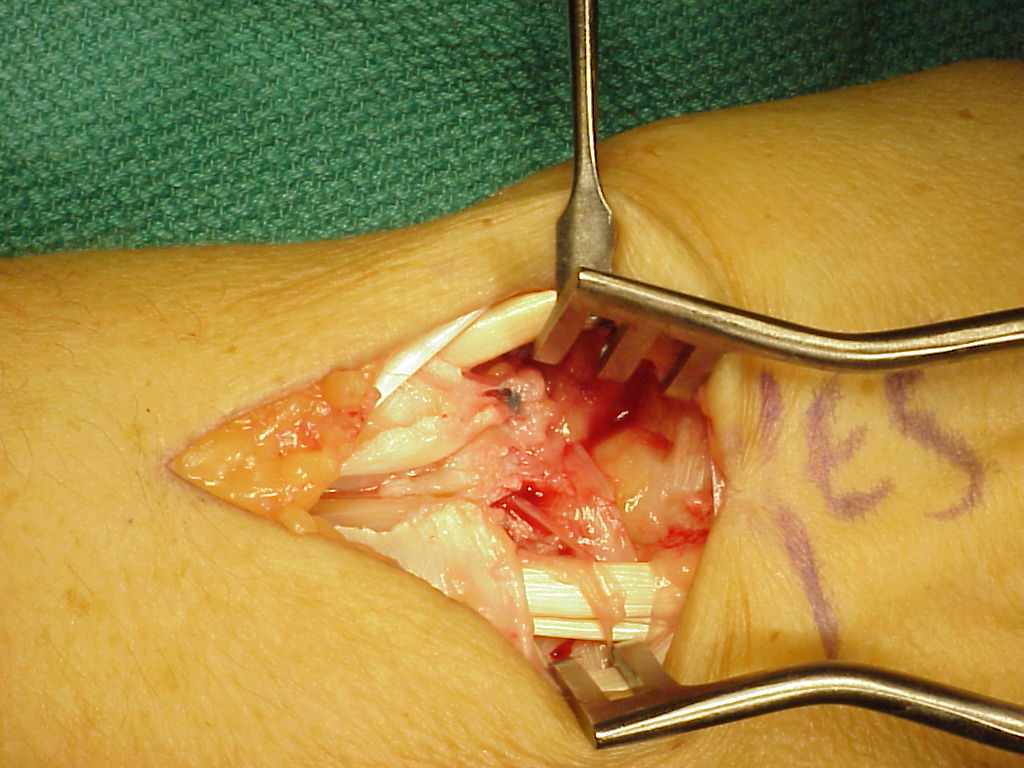

Case 2. Direct repair of scapholunate ligament and retinaculum  transfer (Ragnell retractor beneath). (Right hand, fingers to the right)

Closure of retinaculum showing the area of the donor strip.

Retinaculum transfer. The screws were cut flush with the bone, ends barely visible here in the scaphoid and lunate. (Right hand, fingers to the right)